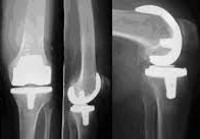

Эндопротез коленного сустава. Хирургические вмешательства, во время которых поверхности суставов, разрушенные вследствие болезни или поврежденные в результате травмы, заменяются искусственными имплантатами. Показаниями для замены сустава являются смещенные внутрисуставные переломы, опухолевые процессы, деформирующий артроз коленного сустава, повреждение сустава после перенесенного гнойного артрита, подагра, псориаз, ревматоидный артрит В зависимости от характера патологического процесса, двигательной активности пациента, его возраста и его веса, можно выполнить тотальную или однополярную артропластику.

Искусственный коленный сустав представляет собой сложную конструкцию из нескольких материалов. Для создания части протеза, который установлен на бедренной кости, обычно используется металлический сплав. Компонент для замены суставной поверхности большеберцовой кости чаще изготавливается из металла и специального пластика. При замене внутренней части коленной чашечки используется пластик.В зависимости от типа установки все эндопротезы можно разделить на имплантаты с цементной фиксацией, протезы с нецементной фиксацией и искусственные швы, при установке которых используются комбинированные методы, которые включают элементы цементной и бесцементной фиксации. Не существует одинаково подходящего для всех «лучших» вариантов эндопротезирования, таких как эндопротез или метод его фиксации. Выбор оптимальной конструкции и способа ее установки производится с учетом возраста пациента, уровня его физической активности, массы тела, состояния здоровья, особенностей патологического процесса в суставе и многих других факторов.

• Тотальная артропластика, которая производит полную замену суставных поверхностей большеберцовой кости и бедренной кости. При необходимости также замените внутреннюю поверхность надколенника во время операции.

• Однослойный протез, где выполняется частичная замена поврежденных или поврежденных суставных поверхностей.